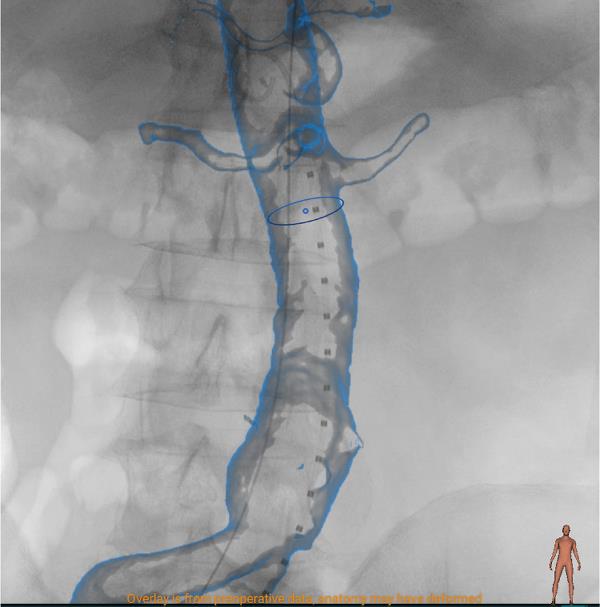

EndoNaut er et intraoperativt 3D-navigationssystem til endovaskulær behandling af aneurismer og stenoser. Den patenterede løsning til 3D-navigation giver dig visuel støtte under operationen og hjælper dig til at udføre indgrebet med stor nøjagtighed og selvsikkerhed. EndoNaut kan let integreres på din operations- eller interventionsstue. Uanset fabrikat.

EndoNaut er et omkostningseffektivt alternativ til en hybrid operationsstue. Udover 3D-billedfusion til aorto-iliaca procedurer giver EndoNaut dig en navigationsløsning til PAD-behandling, der er kompatibel med enhver mobil eller fast C-bue.